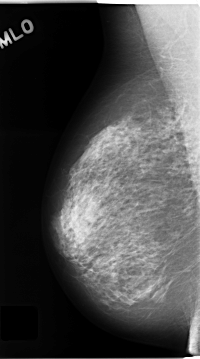

C_0144_1.RIGHT_MLO

RIGHT_MLO LINES 4664 PIXELS_PER_LINE 2592 BITS_PER_PIXEL 12 RESOLUTION 50 NON_OVERLAY